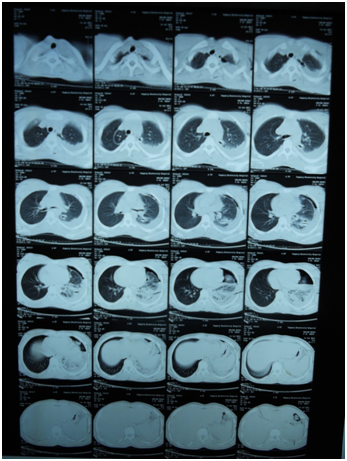

A 17-year-old girl (170cm, 60kg) presented to the emergency department with dyspnea and chest pain after a penetrating stab wound to the chest in the left sixth intercostal space mid-clavicular line, which happened 2hours earlier. Upon physical examination, Pulse was 96 beats per minute and blood pressure was 110/70mmHg, diminished air entry was noticed on the left side of chest. Chest x-ray revealed left hydropneumothorax. Tube thoracostomy was performed left intercostals tube was inserted for drainage. Post-insertion chest x-ray revealed no improvement in the picture of air fluid level (Figure 1) (Figure 2) which was further evaluated by CT that showed fluid collection posteriorly and air anteriorly (Figure 3) (Figure 4). Two days later patient had fever with vomiting and leucocytosis. The nature of the drain from the intercostal tube becomes serosangenous and less hemorrhagic with change in color associated with food. Methylene blue dye (1% concentration) taken orally by the patient was detected in the drain of the intercostal tube two minutes after ingestion (Figure 5). Oral contrast chest x-ray was done, two shots were taken one on swallowing gastrographin, it showed the esophagus outlined without any leakage (Figure 6A). The other shot taken two minutes after oral administration of gastrographin in trendlenberg position, the contrast outlined a track passing from the fundus of the stomach to the left pleural cavity and to the intercostals tube (Figures 6B) (Figure 6C). Laparotomy was performed via midline incision and findings were confirmed. It showed a 3cm orifice of the left copula of the diaphragm with a tear in the gastric fundus which was closed in two layers and the diaphragmatic tear was closed directly with continuous sutures. Two weeks later patient complicated by left empyema with thickened pleura. Thoracotomy was done for complete evacuation of pus and decortication. The patient fully recovered and was discharged 8days after thoracotomy.

Figure 3 CT chest mediastinal window.

Figure 4 CT chest pulmonary window.